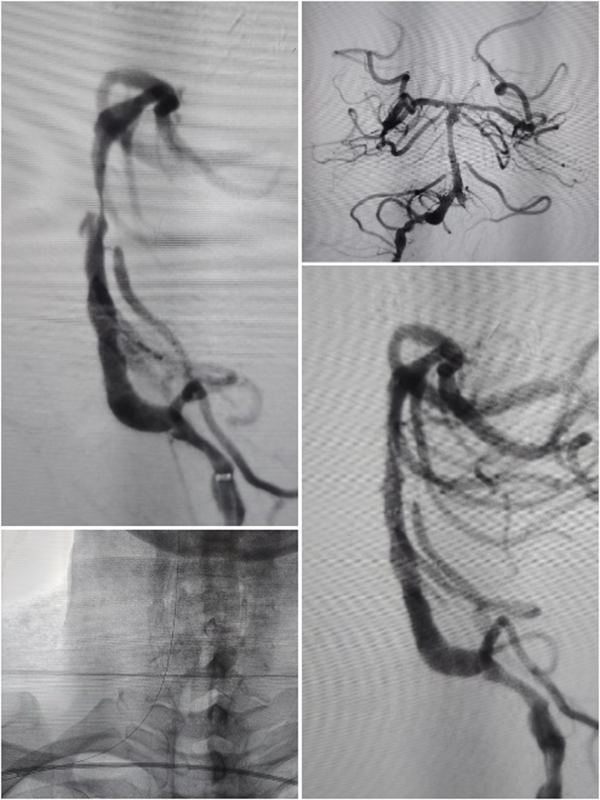

随着时间的推移,一例例复杂的全麻手术被成功完成:

基底动脉夹层管腔线样狭窄

全麻下支架植入术

高龄患者左颈内动脉C7段重度狭窄

全麻下支架术

高龄老人椎动脉长段次全闭塞

全麻下多支架再通术

接着又是两台颅外段头颈动脉支架植入术及7台脑血管造影术……